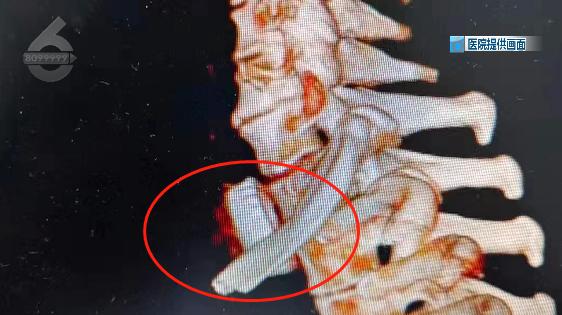

從患者的CT片上看,異物的邊緣成波浪狀,而且非常銳利,在取出的過程中,很容易劃破食管壁造成穿孔或導致頸部動脈大出血,并且由于吞入時間過長,異物已經(jīng)嵌入食道粘膜,在食道鏡下無法取出。

綜合評估異物位置后,為最大程度降低對患者的損傷,耳鼻咽喉科與胸外科會診后,聯(lián)合為李先生采取了頸根部開放式手術,成功將卡在食管上段的啤酒瓶蓋順利取出。